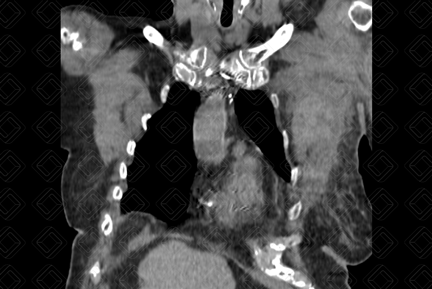

Texto alternativo para a imagem Figura 1. Créditos: Dra. Elazir Mota - Rio de Janeiro/RJ

Descrição das figuras 1, 2 e 3: Tomografia computadorizada de tórax evidenciando lesão heterogênea (seta vermelha) na musculatura peitoral esquerda, espontaneamente densa (densidade ao redor de 65 UH), compatível com hematoma. Paciente fazia uso crônico de anticoagulante.

• Tomografia computadorizada (TC): Observamos aumento volumétrico da musculatura acometida e conteúdo espontaneamente denso no estudo sem contraste (50-80 UH) (figura 1);